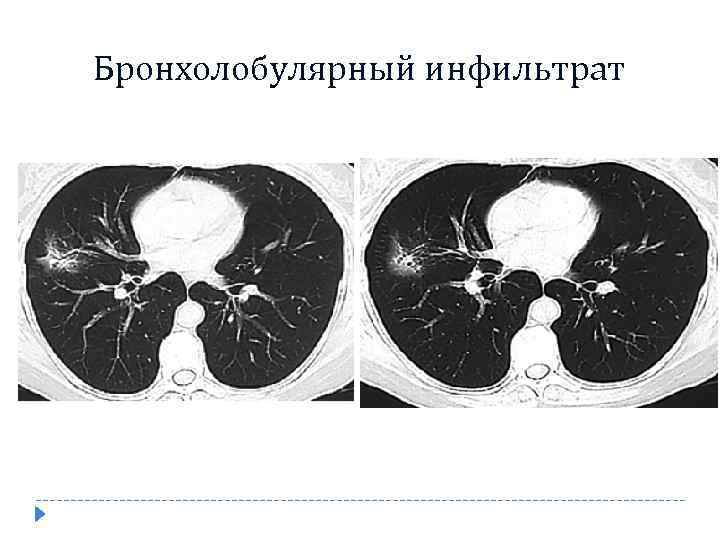

Бронхолобулярный инфильтрат

Бронхолобулярный инфильтрат